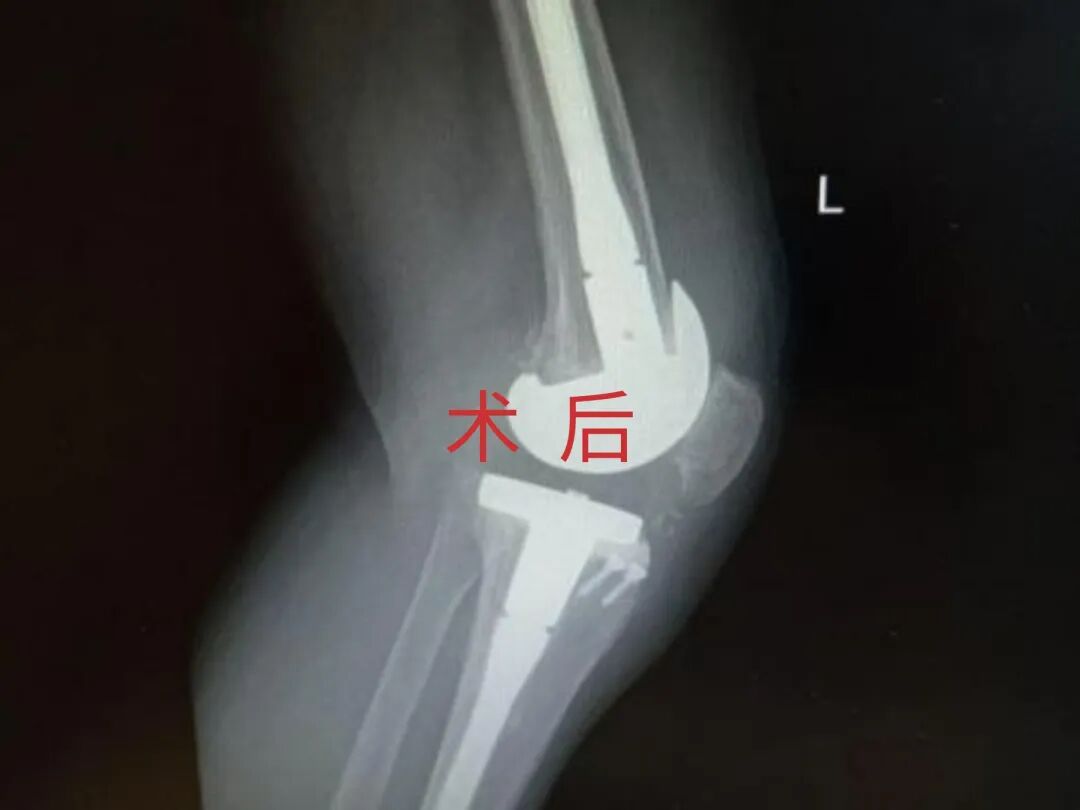

多年来,贵州航天医院各科室紧跟医学前沿,不断强技术、补短板,大力开展新技术、新项目,完成了许多高精尖、高难度、本地区“首例”的技术,填补了医院医疗技术空白,满足了群众日益增长的医疗需求。 贵州航天医院骨科率先在遵义地区开展骨搬移技术,截至目前,已治愈慢性骨髓炎、感染性骨不连、骨缺损、脉管炎、糖尿病足患者200余例,糖尿病足治疗保肢率达到98%。 本期,我们将为大家带来骨科特色技术——骨搬移技术(Ilizarov)。 案例分享 一名59岁的患者,身患糖尿病12年,在来我院3个月前出现了右脚溃烂的症状,来院就诊时,患者的右脚十分红肿,右脚脚趾坏死,伤口处不断流出黑红色脓液,情况十分严重。在接诊到患者时,骨科专家团队高度重视,立刻为患者完善了CT血管造影(CTA)等相关检查,诊断为:2型糖尿病,糖尿病周围血管病变,右糖尿病足。 术 前 考虑到患者情况比较严重,为最大限度保证患者肢体完整,科室专家团队进行了严格的讨论评估,为患者制定了骨搬移技术治疗方案,在征得患者及其家属的同意后,成功通过搬移骨块为患者进行治疗,促进患者病变肢体血管再生。 胫骨横向骨搬移外架固定 清除感染病灶 术后调节外架,通过搬移骨块 促进患肢血管再生 患者在术后三周前来换药,观察到感染得到进一步控制;术后六周复查,患者病变处已愈合,进行CT血管造影(CTA)后可明显观察到足部血管再生。 术后3周 术后6周愈合 CT血管造影见足部血管再生 糖尿病患者全身与局部的问题互为影响,形成恶性循环,糖尿病足溃疡创面迁延不愈,常见干性坏疽、湿性坏疽、趾坏死、深且大的溃疡以及骨髓炎等症状,还可导致脓毒血症,以往为保全生命,患者被迫选择一次或多次截肢。骨搬移技术的发展进步,能在血糖有效控制、局部有效清创下,有效促进患肢微血管再生,改善患肢血供,达到糖尿病足更快治疗康复的目的,并能根据病变情况最大限度的保障患者肢体完整。 什么是骨搬移技术 骨搬移技术是通过使用专用的骨外固定器固定骨段,每天缓慢牵拉,在牵拉搬移过程中,骨段尾部形成新骨及新的软组织,从而修复骨骼缺损及软组织缺损。是治疗大段骨缺损、骨不连、骨感染、肢体畸形的金标准方法,也用于治疗脉管炎、糖尿病足等肢体缺血性疾病。 骨感染缺损 切除感染段 搬移骨段 新骨形成 骨感染根治愈合 骨搬移技术原理 生物组织在持续、稳定、缓慢牵拉下,能刺激细胞分裂、组织再生,骨外固定技术运用该原理,通过持续缓慢调节外固定器形成牵拉张力,促进牵引成骨与相邻组织再生,如神经、血管、肌肉、皮肤等再生,达到治疗大段骨缺损、肢体缺血如糖尿病足等疾病的目的。 骨搬移技术优势 (一)除治疗骨缺损、骨不连外,有更广的适用范围,利用组织再生、血管再生等特性,能大量运用于肢体畸形的矫形、糖尿病足等的治疗。 (二)治疗效果确切,重建肢体外型和功能,极大降低截肢率和残疾率。 (三)明显提高了患者生活质量,极大减轻其家庭及社会负担。 肢体畸形的矫形 慢性骨髓炎 骨段切除 术后1年 濒临截肢的脉管炎术后6周 难愈创面术后3周 贵州航天医院骨科 专家团队 赵学平 骨科主任 主任医师 临床擅长:从事骨科临床工作30余年,对骨科常见疾病的诊治具有丰富的临床经验。 世界中医药联合会脊柱康复专业委员会常务理事,中华中医药学会整脊分会常务委员,中国中西医结合学会骨伤科分会肢体矫形功能重建与康复专家委员会常务委员,中国研究性医院学会骨科创新与转换专业委员会关节外科学组保髋工作委员会常委,中国康复技术转化及发展促进会骨外科与康复技术转化专业委员会常务委员,泛珠三角区域运动医学联盟(PPRD-SMA)理事会常务理事,中国研究型医院学会运动医学专业委员会委员,贵州省中医药学会整脊分会副主任委员,贵州省中西医结合学会银质针专业委员会副主任委员,贵州省康复医学会骨与关节专业委员会常务委员,贵州省人民医院骨科专科联盟常务理事,贵州省康复医学会骨内科专业委员会常务委员,中华医学会贵州省骨科学会委员,贵州省康复医学会脊柱脊髓专业委员会常务委员,贵州省运动医学分会委员,贵州省康复医学会骨与软组织肿瘤专业委员会委员,遵义市医学会创伤分会副主任委员,贵州省康复医学会骨内科专业委员会遵义地区分会常务委员,遵义市医疗事故鉴定、伤残鉴定、工伤鉴定、司法鉴定专家。 长期从事骨科临床研究及教学工作,在国家级、省部级杂志发表论文20余篇,SCI论文2篇,参与主编骨科专著2部,主持省部级科研项目2项,参与指导省部级、市级科研项目6项。 陈明勇 骨科副主任 副主任医师 临床擅长:从事创伤骨科工作约20年,对骨缺损、骨不连、骨肿瘤、肢体畸形等的肢体矫形重建及功能重建,慢性化脓性骨髓炎的根治治疗、糖尿病足的保肢治疗、快速康复理念(ERAS)下的老年骨折的诊治,四肢复杂骨折的诊治,四肢骨折等微创手术治疗具有丰富的临床经验。 2004年毕业于遵义医学院临床专业,曾在中国人民解放军总医院、广西医科大学第一附属医院、上海第六人民医院骨科进修。中国中西医结合学会骨伤科专业委员会横向骨搬移治疗糖尿病足及微血管网再生学组首届委员,遵义市医学会创伤分会常务委员。 瞿 辉 骨科 副主任医师 临床擅长:对骨科的常见病、关节外科、脊柱外科及运动医学疾病的诊治具有丰富的临床经验,熟练掌握骨科手术操作技术。 毕业于遵义医学院临床医学系,2005年前往广州中山大学第一附院骨显微医学部进修学习,2011年前往成都华西医院进修学习,并多次在省内外学习骨科相关知识,是中华医学会骨科分会会员。 赵兴东 骨科 主任医师 临床擅长:擅长骨科的常见病及各种创伤、四肢骨折创伤修复、骨感染、手足疾病的诊治和手足体表畸形的矫形整复,熟练掌握骨科四肢骨病及创伤的手术操作技术,尤其在四肢关节复杂性损伤、手足外伤、组织缺损创面、难治创面的皮瓣修复方面及平足、高弓足矫形方面及四肢慢性疼痛诊治、康复方面具有丰富的临床经验。 硕士研究生,毕业于遵义医学院临床外科系,2015年前往山东省立医院手足外科进修学习;遵义市医学分会创伤分会第一、二届委员,遵义市手外科医学会第二委届员会常务委员;在省级及省级以上期刊发表文章9篇,参编著作2部,参与主持并完成市级课题1项,参与市级课题2项、省级课题1项。 张俊凯 骨科 副主任医师 临床擅长:从事骨科临床工作28年,对创伤骨折、骨感染、骨缺损、骨不连等外科诊治,四肢骨折的微创手术治疗,四肢复杂骨折(如关节内粉碎性骨折、多发骨折等)的损伤控制及手术治疗等具有丰富的临床经验。 1995年毕业于遵义医学院临床专业,2009年前往复旦大学附属医院骨科进修1年。 卢懿明 骨科 副主任医师 临床擅长:从事骨科工作18年,对创伤骨折、四肢骨折的微创手术治疗、四肢复杂骨折(如关节内粉碎性骨折、多发骨折等)的损伤控制及手术治疗,尤其是髋部骨折的PFNA等微创技术,踝关节骨折、膝关节周围骨折的Mipo微创技术等具有丰富的临床经验,开展了4项新技术,发明6项新型专利技术。 2005年毕业于遵义医学院临床专业,2017年,前往南方医科大学第三附属医院骨科进修半年,回院后运用Mipo技术对骨干骨折及干骺端骨折的治疗技术,同时积极开展骨盆骨折、髋臼骨折腹直肌外侧切口的应用;发表了多篇专业论文,经常参与省内外学术交流会授课,获得医院荣誉称号多个。 邬夏荣 骨科 副主任医师 临床擅长:从事骨科工作16年,对四肢复杂骨折、骨肿瘤的诊治,尤其是足踝创伤、慢性踝关节损伤、平足症等诊疗具有丰富的临床经验。 2006年毕业于遵义医科大学临床医学专业,曾在陆军军医大学西南医院进修学习,发表多篇骨科学术论文。 余德怀 骨科 副主任医师 临床擅长:从事骨科工作10余年,对运动医学、骨关节、脊柱外科常见病、多发病的诊治具有丰富的临床经验。 硕士研究生,2011年毕业于遵义医学院临床医学专业,曾前往遵义医科大学附属医院运动医学专业进修学习;是贵州省医学会运动医学分会青年委员,西部关节镜联盟委员;发表多篇骨科学术论文。 冯 乾 骨科 副主任医师 临床擅长:从事骨科工作近20年,熟练掌握骨科多发病及常见病的诊治,尤其对脊柱退变性疾病的诊断及治疗具有丰富的临床经验,主要研究脊柱微创相关治疗方式,能熟练开展椎间孔镜及VBE。 曾前往北京大学第三医院进修学习疼痛及椎间孔镜、首都医科大学友谊医院专业进修脊柱内镜;是贵州省康复医学会第三届脊柱脊髓专业委员会委员;发明专利3项、发表脊柱外科专业论文多篇。 张艳金 骨科 副主任医师 临床擅长:从事骨外科工作16年,对复合伤、多发伤的救治、四肢骨干骨折、关节周围骨折、骨肿瘤、骨髓炎等诊治具有丰富的临床经验。 中共党员,硕士研究生,2006年本科毕业于山西医科大学第二临床医学院,2011年研究生毕业于北京军区总医院;在“老年COPD患者合并髋部骨折的诊治”国际合作课题组研究两年,在老年髋部骨折的诊治方面具有丰富的经验,并发表论文6篇;承担遵义市级课题1项;承担遵义医科大学的临床教学工作,获得遵义医科大学优秀带教老师荣誉。编撰有《骨科疾病诊疗精粹》一书,开展2项新技术,编撰地方规范《务川自治县创伤骨科常见疾病诊疗规范》一书。 赵小锋 骨科 副主任医师 临床擅长:从事骨科临床工作11年,对骨科常见病、多发病诊疗有较为丰富的临床经验,擅长脊柱相关疾病诊断及治疗,尤其是颈、腰、腿疼痛疾病诊断及治疗,擅长胸腰椎骨折微创经皮穿刺内固定术、经皮穿刺椎体成形术、经皮穿刺脊柱内镜下腰椎间盘摘除术、单纯开创腰椎间盘摘除术、腰椎滑脱复位椎间植骨椎融合内固定术、腰椎管狭窄减压融合内固定术及人工髋、膝关节置换术等。 2012年毕业于遵义医学院外科学专业硕士研究生,2019年参加“遵义市115医学人才精英计划”于上海交通大学第一附属医院培训学习,2023年于北京大学第三人民医院脊柱外科进修学习,曾获得遵义市优秀医师荣誉称号。 遵义市手外科第一届委员,遵义市医学会创伤分会第一届委员,遵义市医学会创伤分会第二届委员,贵州省康复医学会第三届脊柱脊髓专业会委员,遵义市医学会烧伤与整形外科学分会委员,发表论文5篇,其中国家级核心期刊1篇,SCI论文1篇,主持市级课题1项并结题,参与市级课题2项。 贵州航天医院骨科简介 基本情况 贵州航天医院(原3417医院)骨科组建于1968年,前身是以创伤和断肢(断指)再植闻名于世的上海市第六人民医院骨科,中国断肢(断指)再植的奠基者、中科院院士陈仲伟等著名专家、学者多次莅临科室指导医疗、教,是贵州省最早拥有专业骨科技术科室之一,在70年代开展了贵州省首例断肢(断指)再植手术。组建50余年来,诊治患者已逾百万,挽救了无数的伤病员,成为了保障遵义地区人民群众健康的重要支撑。 经过几代人的不懈努力,今天的骨科,已由创伤骨科发展至骨病、骨肿瘤、骨结核等领域,现有脊柱外科、关节外科、四肢创伤、手足外科四个亚专科,成为了集医疗、教学、科研于一体的综合学科,是贵州省临床重点专科、遵义市临床重点专科、遵义市骨科临床医学中心、遵义市基层骨科专科联盟理事长单位。 科室目前开放床位110张,共有医护人员50余人,副高级以上专家18人,硕士研究生15人。拥有一流骨科医疗设备多台,每年不定期选派优秀技术骨干到全国各大知名医学院校进修、学习、参观、交流,并邀请国内、国外知名专家教授来院进行交流、指导,通过不断引进国内外先进的诊疗技术,科室医疗技术水平稳步提升,为广大人民群众提供了优质的医疗服务。 专科特色 骨一科 (一)骨缺损、骨不连的肢体与功能重建 胫骨横向骨搬移技术治疗糖尿病足: (二)慢性骨髓炎的根治治疗 (三)肢体缺血性疾病如糖尿病足、脉管炎的保肢治疗 (四)皮瓣修复 (五)复杂创伤的治疗 (六)老年髋部骨折及小儿骨折快速手术 老年髋部骨折: 骨二科 (一)胸腰椎骨折微创经皮椎弓根螺钉固定术 (二)老年性骨质疏松性患者腰椎滑脱脊柱内固定术(骨水泥螺钉) (三)V形双通道脊柱内镜技术(VBE)腰椎融合术治疗腰椎退行性疾病 (四)老年性骨质疏松性骨折(PVP/PKP)术 (五)人工髋关节置换术 (六)双侧股骨头坏死人工全髋关节置换 (七)右侧全髋置换术后假体周围骨折翻修 (八)人工膝关节置换术 (九)人工膝关节假体松动翻修 (十)关节镜技术 传统手术切口 关节镜技术切口 诊疗范围 骨一科 1.四肢创伤、矫形。 2.手、足踝外科。 骨二科